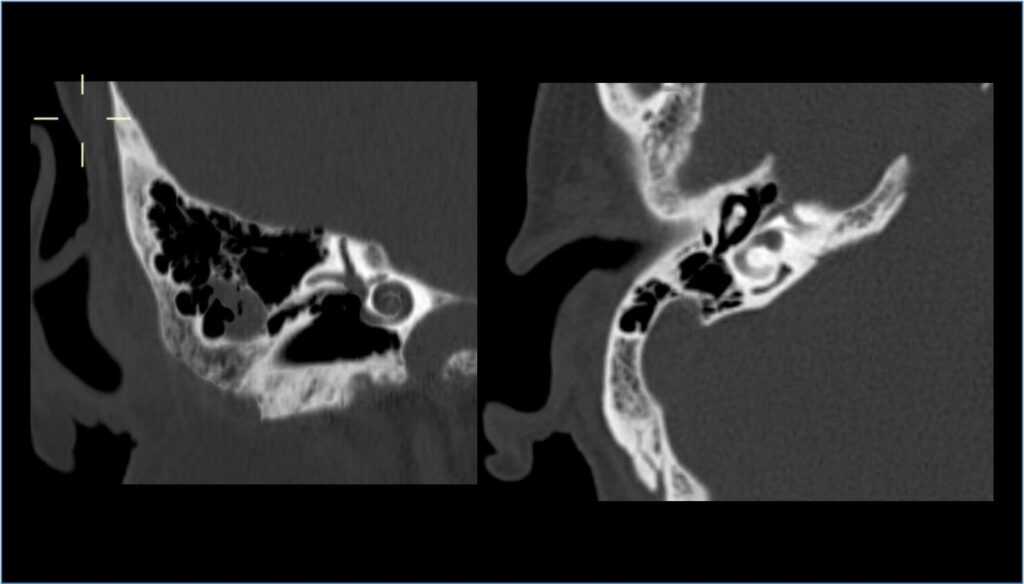

TC orecchio

Cos’è? E’ un’indagine radiologica che, tramite l’utilizzo dei raggi X, permette lo studio delle strutture ossee dell’orecchio e delle strutture nervose dell’angolo ponto-cerebellare, in maniera